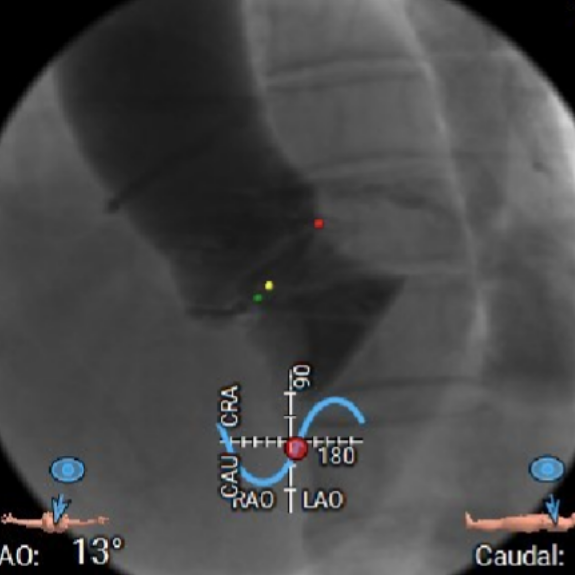

释放体位

主瓣二尖瓣分开体位